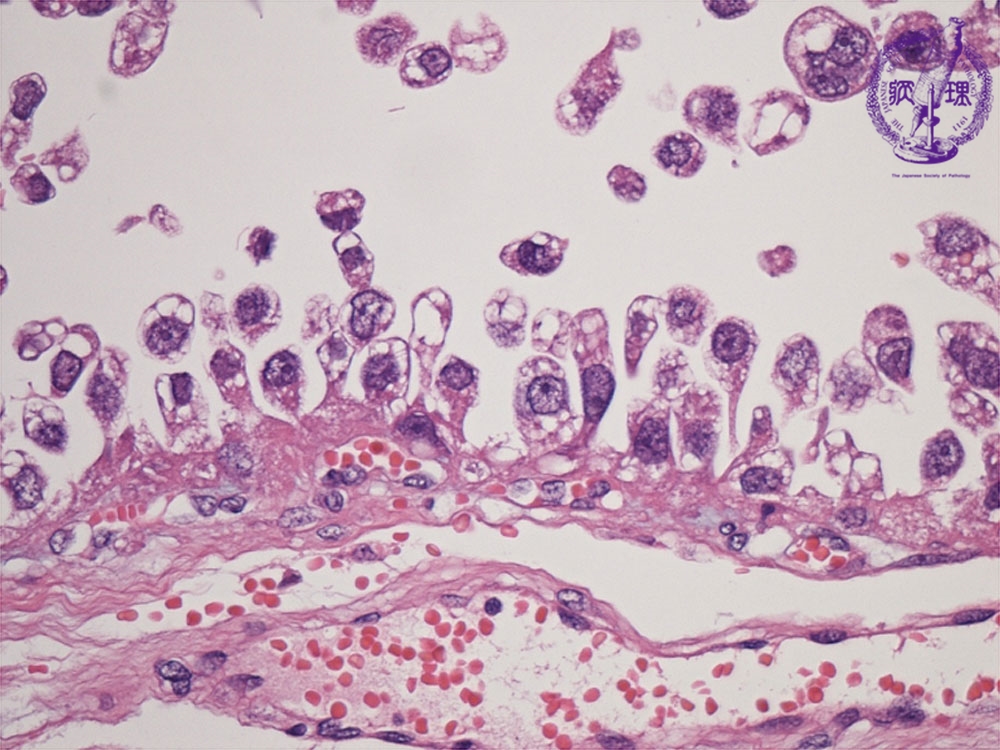

- (8)Clear cell adenocarcinoma of the ovary

Histology (HE stain, high power): Carcioma cells with clear cytoplasm proliferated showing hobnail patterns (nuclei is located at free end of cancer cell as if protruding, red dotted line). The term Hobnail originated from the resembalance between the shape of these cells and the nails with thick head for boot soles.